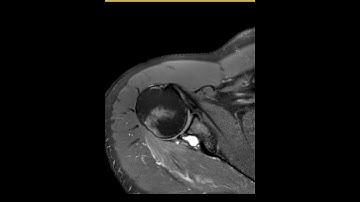

Suprascapular Nerve Decompression Case - Part 5